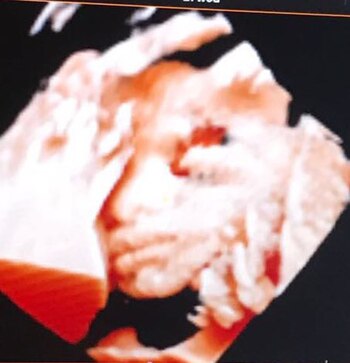

Cada vez falta menos y, a pesar de que vive "un súper embarazo", la ansiedad se hace notar; embarazada de siete meses, Jesica Cirio (32) se realizó una ecografía 4D.

"Estoy re bien, tengo un súper embarazo, no me puedo quejar. En ningún momento sufrí, no tuve vómitos, nada. Estoy un poco ansiosa, ya en la recta final, esperando el momento", confesó la modelo, conductora e instructora de Zumba a Teleshow.